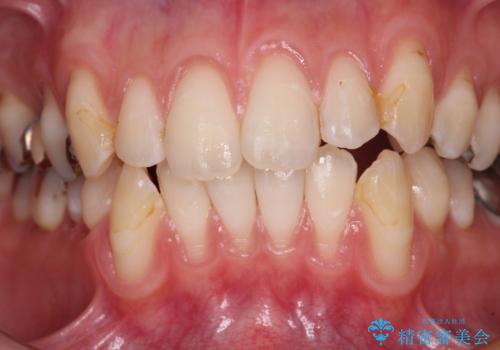

- 歯肉退縮による知覚過敏を気にして来院された患者様です。

診察したところ、知覚過敏をむし歯と勘違いし、一生懸命磨いたことで横縞模様ができるほどでした。

歯肉退縮に対して、上顎からの結合組織移植術(CTG)により、歯根の被覆を行うとともに、歯肉の厚みを増すことで将来の退縮リスクを抑制することとしました。